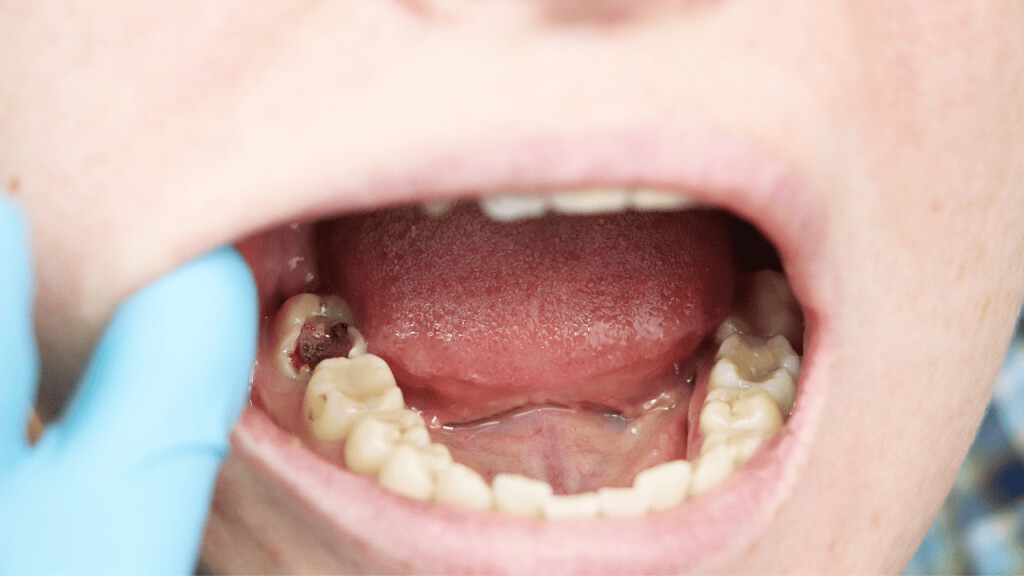

A loose tooth can be very annoying and discomforting. Your oral hygiene, gum disease, teeth grinding, hard food, mouth injury, anything can result in a loose tooth. You can let your tooth come out on its own. But the issues that come with that, like problems in eating food, constant sensitivity, etc can be hard to bear. And you just can’t keep waiting for your tooth to fall on its own for a long time. So, how to get a tooth out in a fast and painless way?

How to pull an adult tooth out without pain?

There are a few ways through which you can pull out a loose tooth without hurting yourself. However, if you are experiencing any kind of inflammation or pain, it is advisable that you visit a dentist.

These are a few ways to get a tooth out in fast and painless ways. But the process doesn’t stop here. Aftercare of your gum is very important.

Aftercare tips after pulling out a tooth

Pulling out a tooth can be quite painful and finding a little blood on the spot is common. Here are a few care tips after pulling out the loose tooth.